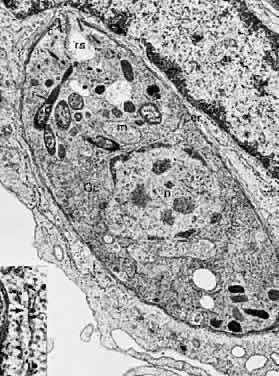

Toxoplasma gondii has a primitive type of mouth referred to as a conoid. This organelle is extended as the parasite “searches” for a host-cell and makes contact with the plasmalemma of a potential host cell immediately before entry. The work of Nichols and associates58 shows that rhoptries, other specialized organelles that are thought to contain lytic enzymes, protrude anteriorly into the conoid and fuse with the limiting membrane of the conoid just before the entry of the parasite into a host cell. Discontinuities develop in this membrane, through which the contents of the rhoptries appear to be discharged. After discharge, the rhoptries resemble empty sacs (Fig. 4). At the site where the conoid indents the host cell, phospholipid vesicles are formed in the plasmalemma of the host cell and a small discontinuity can be seen to develop in this membrane.34 The parasite then squeezes through this opening until it is totally enveloped within the cytoplasm of the host cell. The site of perforation subsequently shows a healing over or restoration of the continuity of the plasmalemma. The conoid of the parasite then retracts to its normal resting position.

Fig. 4. A longitudinal section through a T gondii organism that has recently invaded a host cell. The inset at higher magnification illustrates ribosomes (r*) attached to the endoplasmic reticulum (white arrow). (× 28,400; inset × 81,000.) n, nucleaus; Gc, Golgi's complex; m, mitochondrion; er, endoplasmic reticulum; c, conoid; r, rhoptry; rs, rhoptry sac.